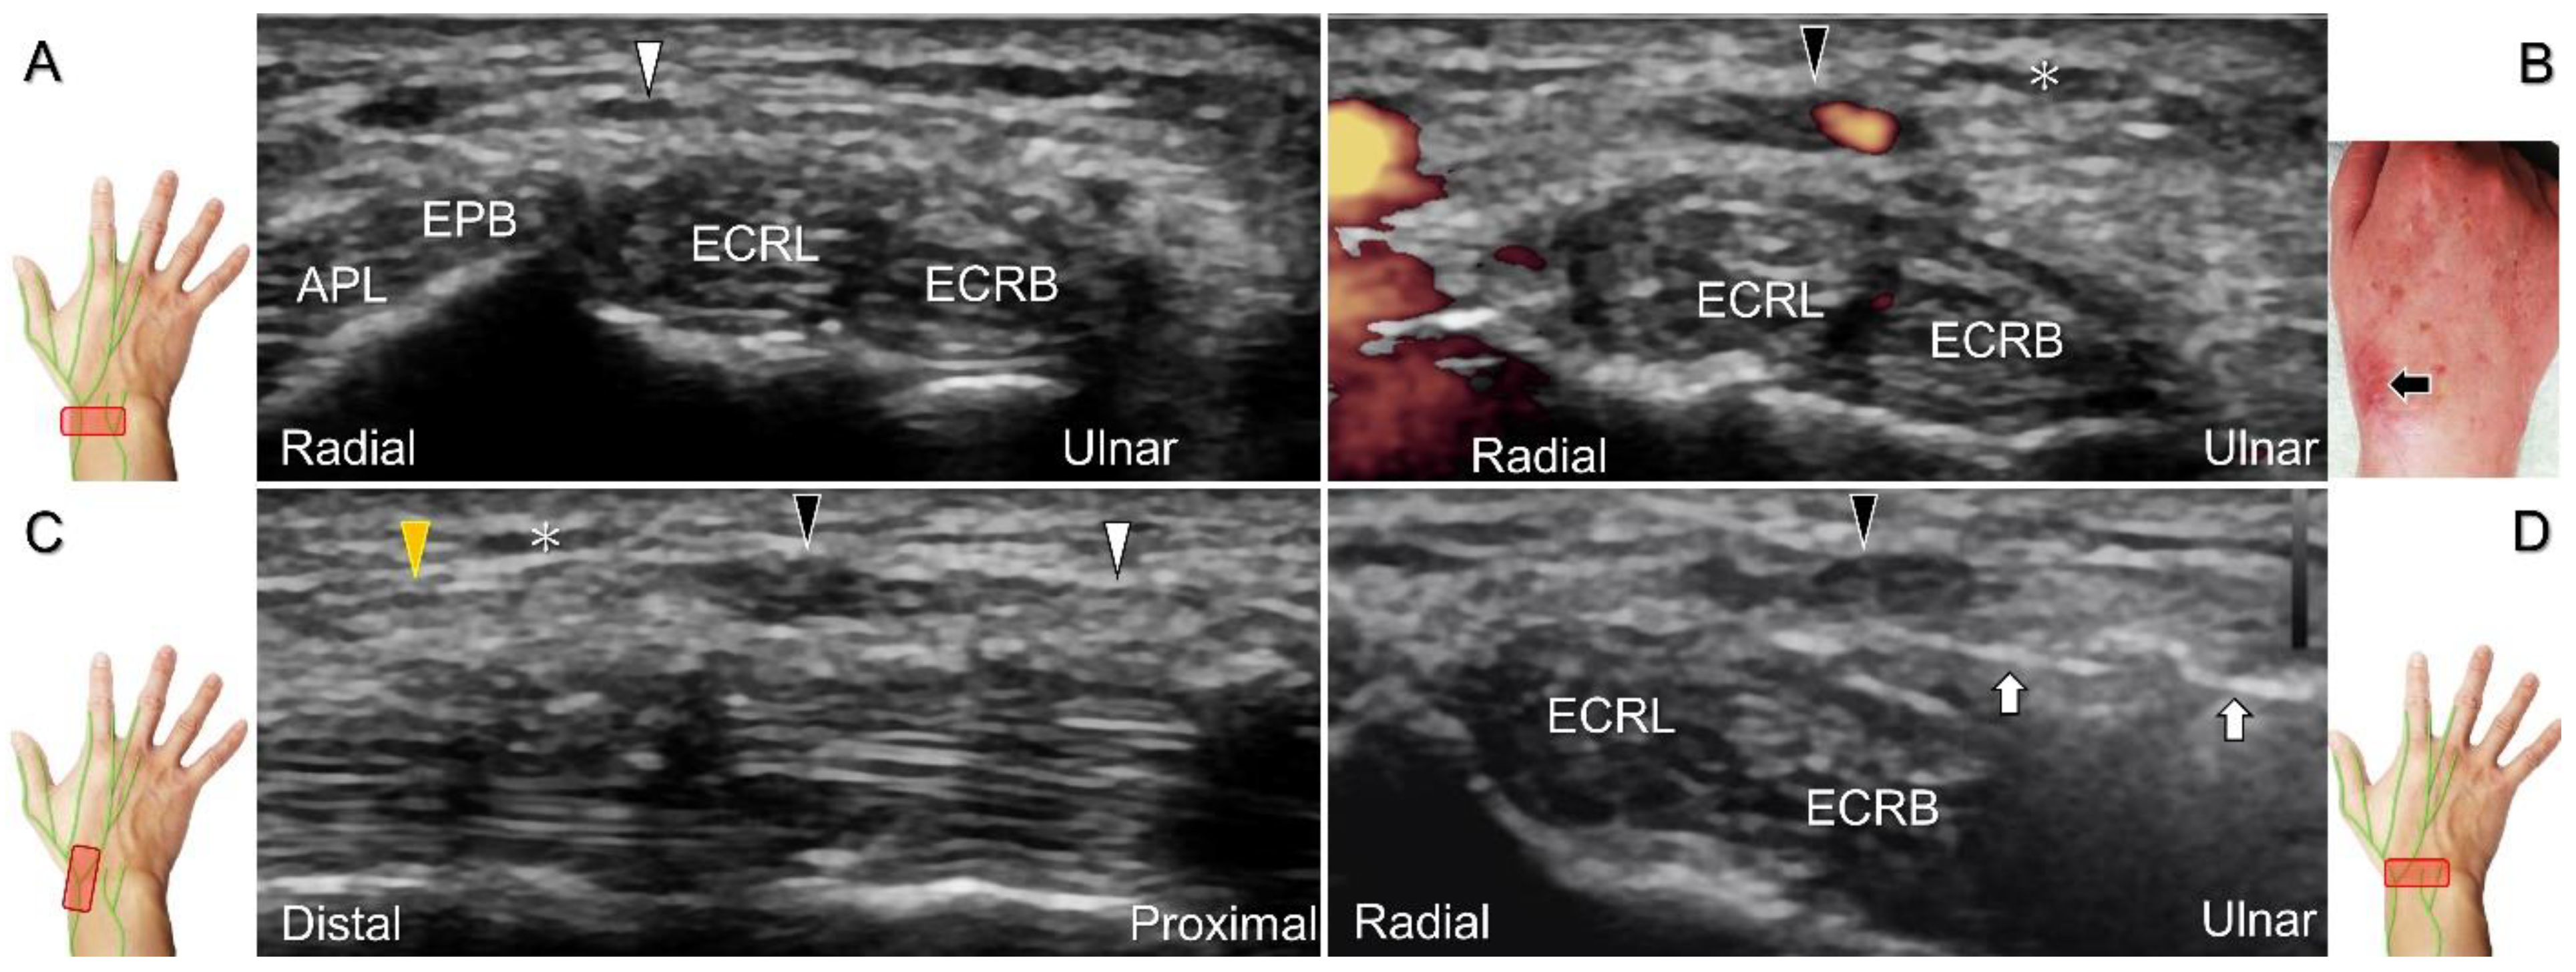

Scanning Technique

With the forearm supinated, the transducer is positioned in the axial plane at the lateral aspect of the antecubital fossa. The superficial and deep radial nerves are situated between the brachioradialis and brachialis muscles. The superficial radial nerve initially courses next to the radial artery below the brachioradialis muscle, and then departs from the radial artery in the distal third of the forearm (Figure 21A). Distally, it pierces the antebrachial fascia between the extensor carpi radialis longus and brachioradialis tendons. When tracking the terminal portion of the superficial radial nerve, the forearm can be pronated, as it courses toward the dorsal radial aspect of the wrist/hand. The superficial radial nerve travels above the proximal intersection junction between the first and second dorsal extensor compartments (Figure 21B). Later, it divides into the dorsomedial and dorsolateral branches. The former courses above the distal intersection junction of the second and third compartments (Figure 21C). The latter runs beside the extensor pollicis longus tendon (Figure 21D).

Additionally, acupuncture and cannulation of the cephalic vein over the distal forearm can lead to nerve injury. To prevent iatrogenic injury, the superficial radial nerve before injection should also be recognized for de Quervain’s syndrome (Figure 23A) [44], ganglion cyst aspiration (Figure 23B), and catheterization (Figure 24A–C). For injection of the superficial radial nerve, an in-plane approach in the nerve’s short axis is preferred (Figure 24D).

Figure 21. Sonographic imaging (short-axis view) of the superficial radial nerve from the distal third of the supinated forearm (A). With the pronated forearm, the nerve is seen to travel above the proximal intersection junction (B), divide into the dorsomedial branch coursing above the distal intersection junction (C), and the dorsolateral branch running beside the extensor pollicis longus tendon (D). Arrowheads: superficial radial nerve; white arrow: dorsomedial branch; black arrow: dorsolateral branch. RA: radial artery; APL: abductor pollicis longus tendon; EPB: extensor pollicis brevis tendon; ECRL: extensor carpi radialis longus tendon; ECRB: extensor carpi radialis brevis tendon; EPL: extensor pollicis longus tendon; C: cephalic vein.

Figure 22. Sonographic imaging (short-axis view) of the dorsolateral branch of the superficial radial nerve at normal (A), swollen (B), and compressed (C) segments. White arrowhead: normal segment; black arrowhead: swollen segment; orange arrowhead: entrapped segment. ECRL: extensor carpi radialis longus tendon; ECRB: extensor carpi radialis brevis tendon; EPL: extensor pollicis longus tendon.

Figure 23. Sonographic imaging of the superficial radial nerve beside the first extensor compartment of the wrist (A), and a ganglion cyst over the second extensor compartment of the wrist (B). White arrowheads: superficial radial nerve; white arrow: needle. APL: abductor pollicis longus tendon; EPB: extensor pollicis brevis tendon; ECRL: extensor carpi radialis longus tendon; ECRB: extensor carpi radialis brevis tendon.

Figure 24. Sonographic imaging of the superficial radial nerve entrapment due to a post-surgical scar. Short-axis imaging at the normal (A) and the swollen (B) segment proximal to the entrapment. The normal, swollen, and entrapped segments of the nerve are seen in long-axis view (C). Ultrasound-guided hydrodissection of the nerve from the ulnar aspect (D). White arrowheads: normal segment; black arrowheads: swollen segment; orange arrowhead: entrapped segment; white arrows: needle; black arrow: scars on the skin; asterisk: scars in the subcutaneous tissue; APL: abductor pollicis longus tendon; EPB: extensor pollicis brevis tendon; ECRL: extensor carpi radialis longus tendon; ECRB: extensor carpi radialis brevis tendon.